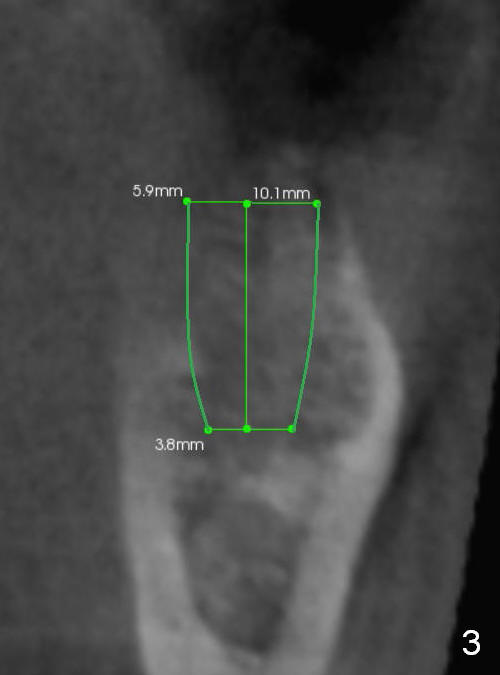

A 44-year-old black lady is a typical dental phobic. She has lost #19 for years with history of traumatic extraction. The ridge is atrophic (Fig.1). She is not comfortable with intraoral X-ray. So CBCT is taken. The coronal section shows that the bone density is low in the coronal ridge (Fig.2 arrowheads). It is difficult to determine the buccolingual width at crest; probably a 5.9x10 mm implant is appropriate (Fig.3). The most useful information from CT is height determination for the implant (Fig.4). The initial osteotomy depth is 10 mm (Fig.5); there is a large safety margin. There is a 2 mm clearance when a 4.5x12 mm implant is placed (Fig.6). Incision is sutured; a 8x4 (3) mm healing abutment is placed (Fig.7 arrowhead), followed by application of perio dressing. The latter remains stable 13 days postop thanks to the holding effect of the healing abutment (Fig.8 H). The wound has apparently healed when the dressing is removed (Fig.9). It appears that the edentulous space is extremely wide. The 4.5 mm implant may not sustain masticatory force. Limited orthodontic treatment appears to be necessary, using the implant as an anchorage to move the neighboring teeth (Fig.10 arrows). In fact the orthodontic treatment is not rendered. A crown is cemented 14 months postop. The cortical bone is thickened around the implant 15 months post cementation (Fig.11).